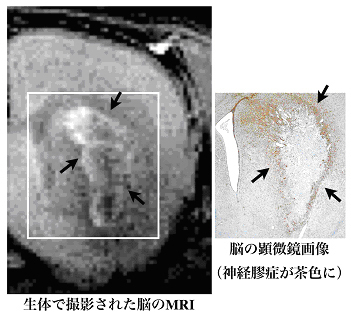

これまで,神経膠症(グリオーシス)の発生を確認するには,死後に脳を摘出し,薄い切片を作成して顕微鏡で観察することしか方法がなかった。今回の研究では,マンガンイオンを利用した造影剤を使って,生きたまま脳のMRI(磁気共鳴画像)を撮影することで,脳梗塞の実験モデルで,傷害部位を取り囲むように発生した神経膠症(グリオーシス)を,白い信号上昇として検出することに成功した(図)。

研究グループは,脳梗塞で生じた神経膠症(グリオーシス)を可視化するため,MRI(磁気共鳴画像)の造影剤の一つであるマンガン造影剤に注目した。マンガン造影剤は,活発な細胞に多く取り込まれ,また細胞の密度が高い場所で,高いMRI信号を出すという特徴がある。そこで麻酔下のラットを対象に実験的な脳梗塞を作成し,この脳梗塞モデルのラットに対してマンガン造影剤を使用した。約3週間の間に見られる脳の変化を高磁場MRI※6を使って画像化した。すると,梗塞の発症から10日目以降に,神経の傷害部位を取り囲むような白い信号(信号上昇)が見られることを発見した(図)。組織染色と比較することで,この信号上昇が見られた部位が神経膠症(グリオーシス)の起こっている場所であることを確定した。

(図)マンガン造影剤によるグリオーシスのMRI(マンガン増感MRI)

脳梗塞が起きた場所を取り囲むように環状に高い信号がある。組織染色と比較して,主にアストログリアによる神経膠症(グリオーシス)であることが判明。また,炎症の反応としてミクログリアの集積も観察された。これを食い止めるかのように,アストログリアによる神経膠症(グリオーシス)が防波堤を形成している。高磁場MRIでは,脳梗塞の傷害部位を100ミクロンの精度で画像化できる。